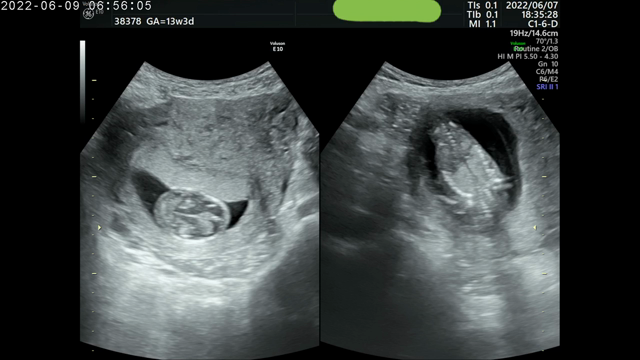

性別が気になる②14週妊婦 R先生(ベビーナブ)1回目の性別判定

2022年6月10日